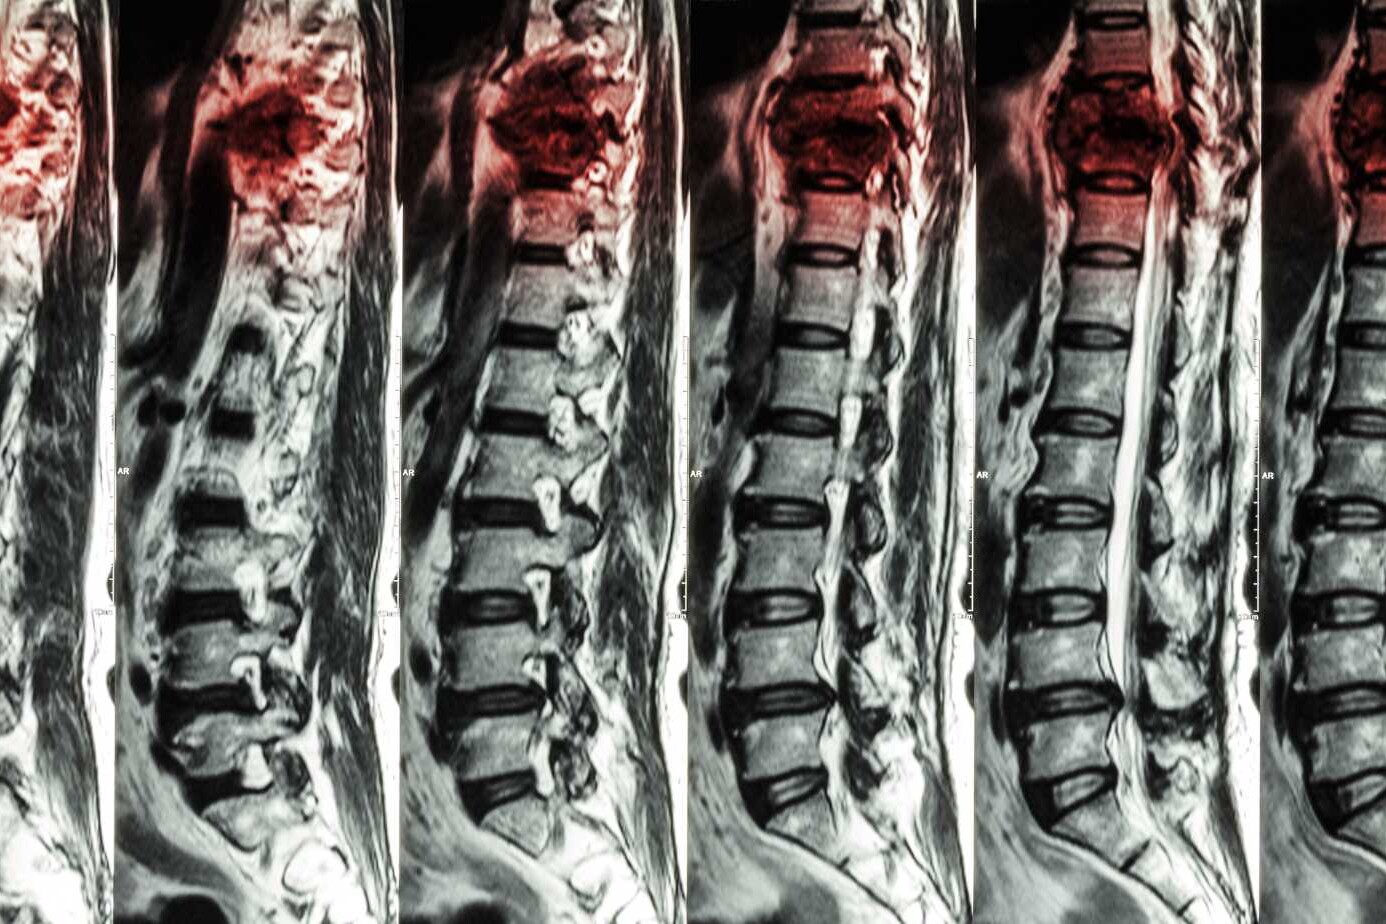

- Comprehensive Diagnostic Evaluation (medical history, neurological exam, cervical MRI/X-ray, posture analysis, screening for disc or nerve issues)

Often, yes. MRI scans provide a clear view of discs, nerve roots, and the spinal cord. This helps Dr. Chugh identify hidden problems like bulging discs or nerve compression. The scan supports a more precise and customized treatment plan